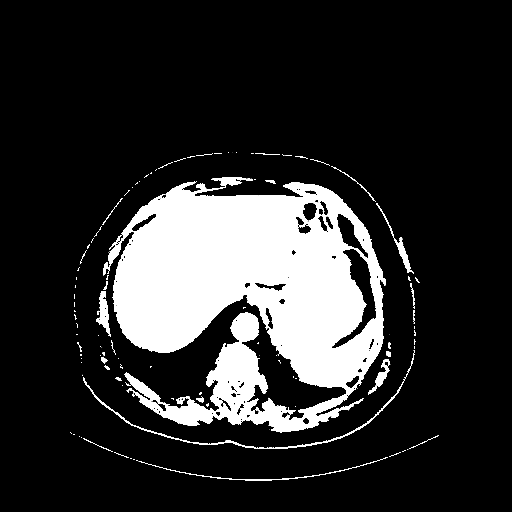

Original NATIVE CT scan (input)

Full window (WL 1023.5, WW 4095 β†’ Low βˆ’1024, High +3071)

Actual HU range: [-1024.0, 3071.0]